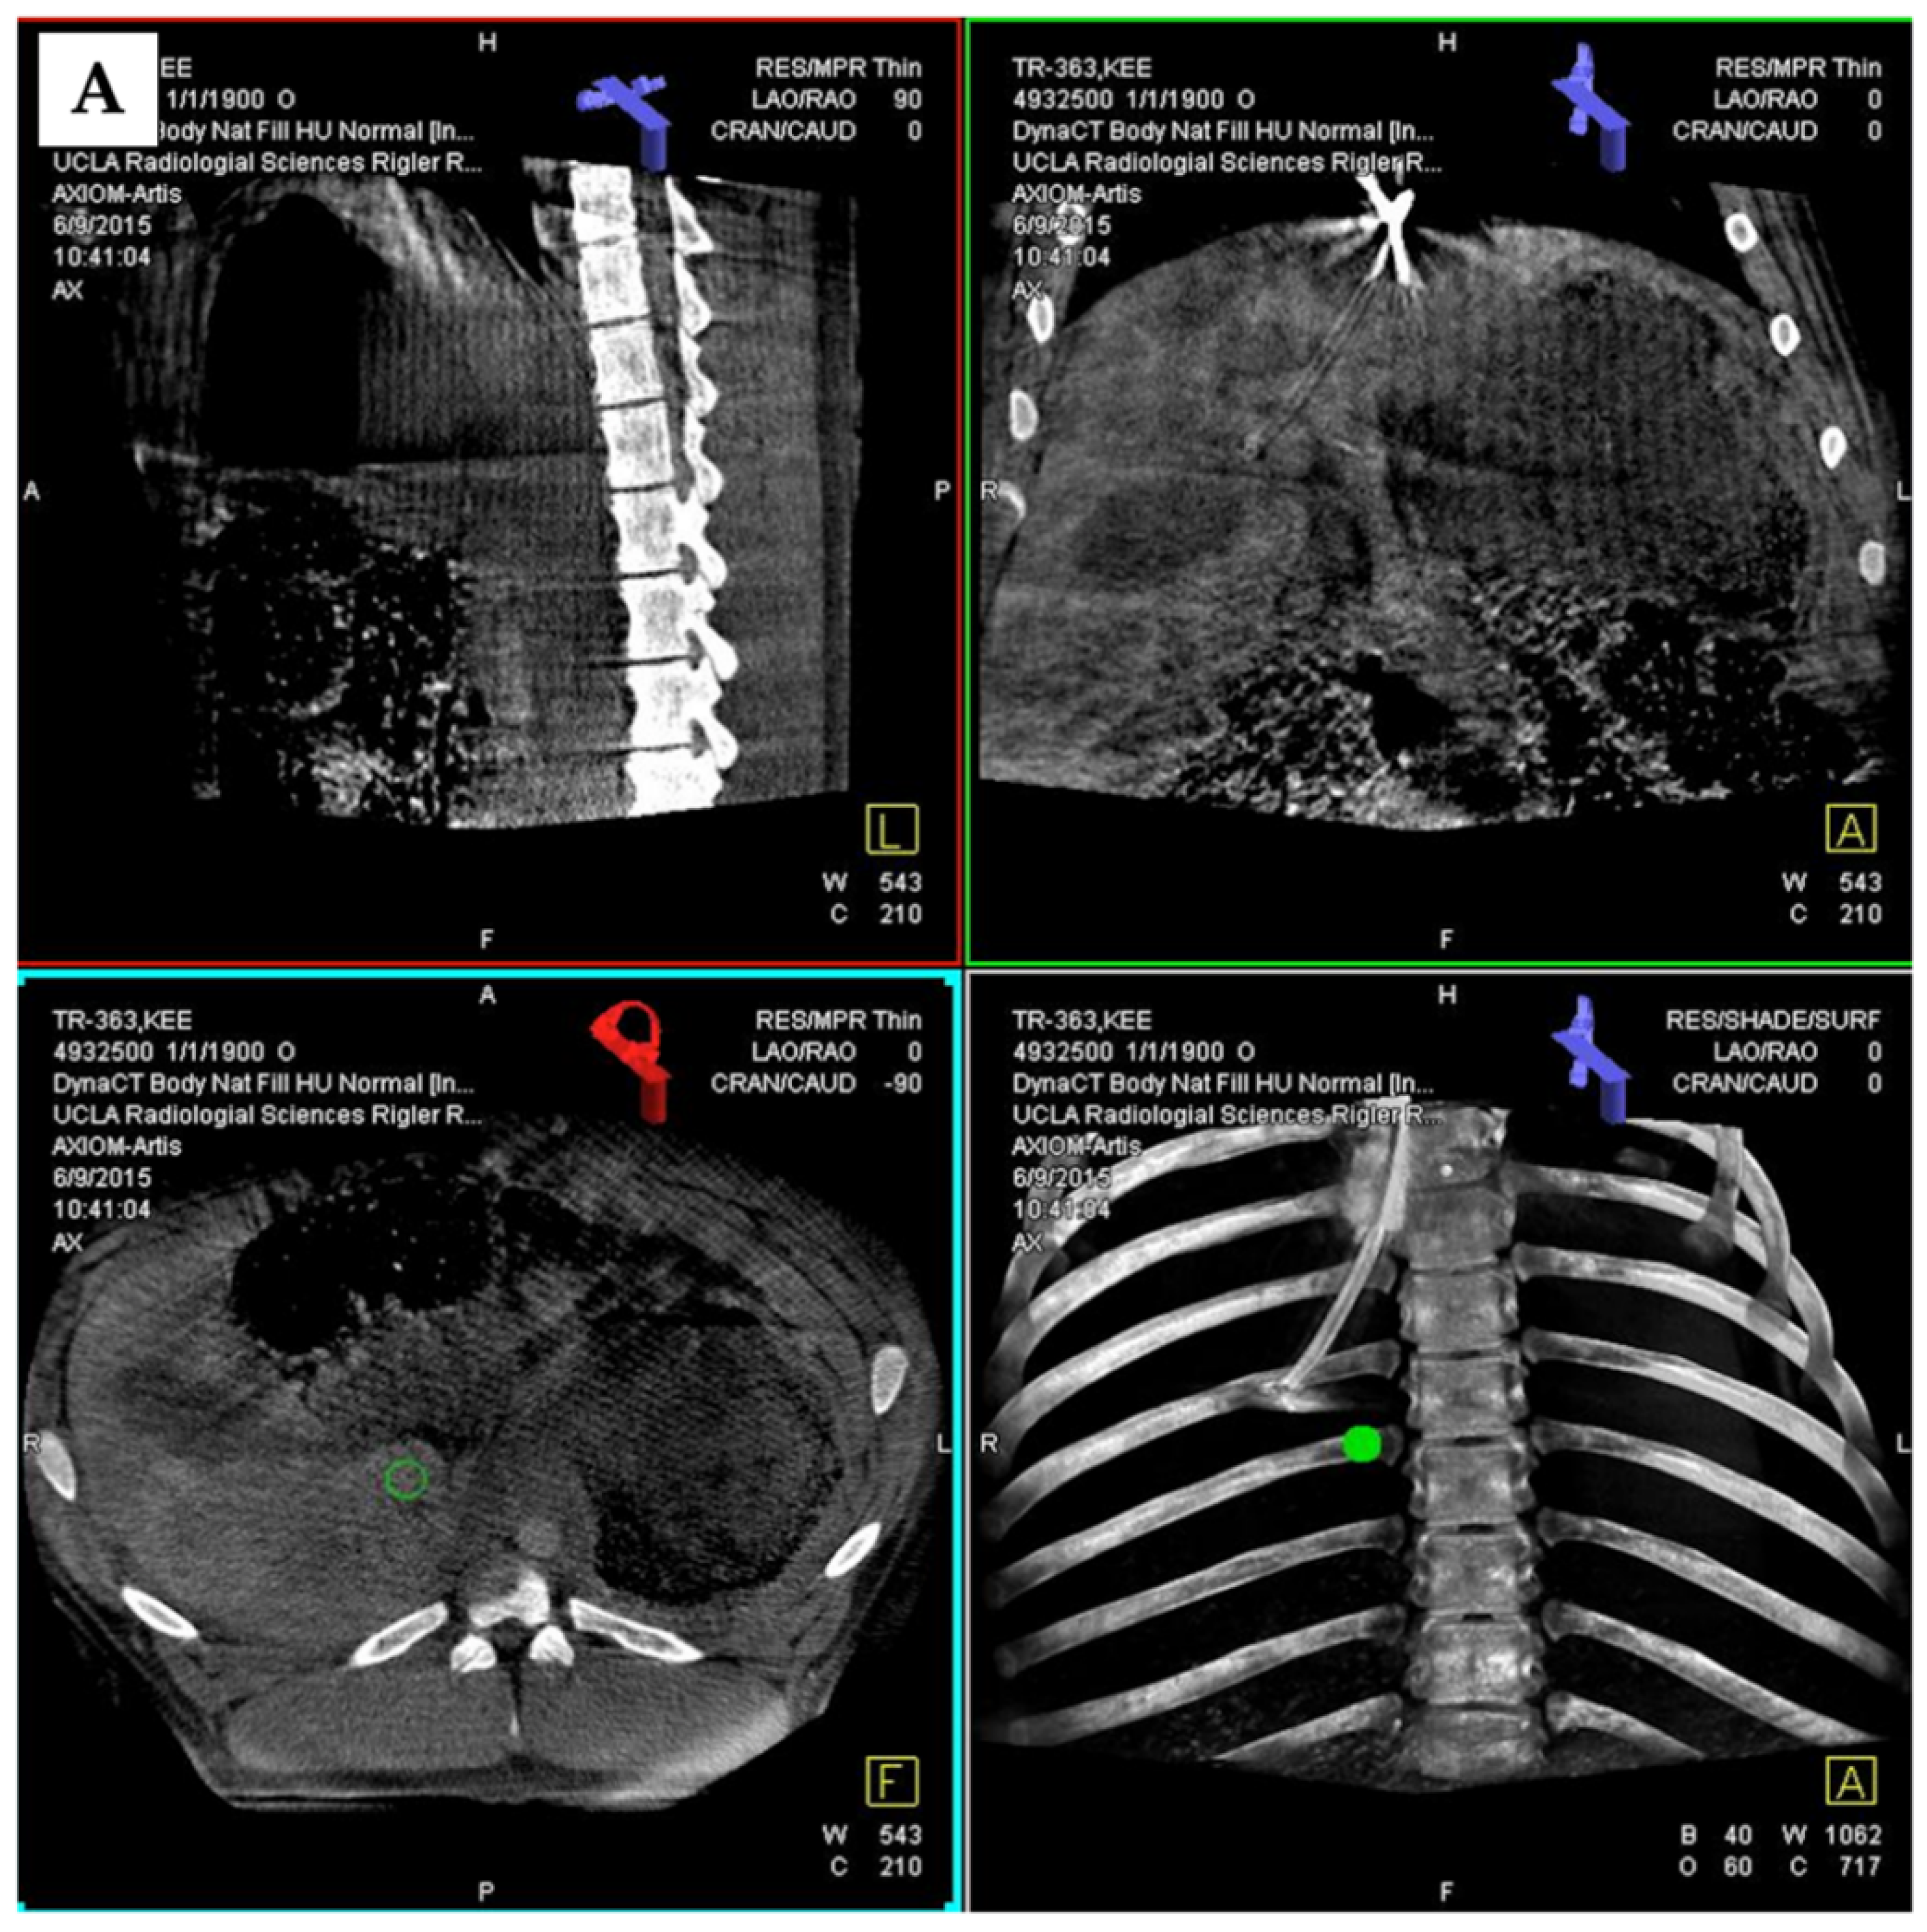

2.4. Cone Beam CT Imaging

2.5. TIPS and DIPS Creation Using 3D Image Guidance

3.2. 3D Angiography-Guided TIPS Procedure Using Pre-Procedural Cross-Sectional Imaging with CBCT/Angiography-Fused Images

3.3. 3D Angiography-Guided TIPS Using CBCT/Angiography-Fused Images

3.4. 3D Angiography-Guided DIPS Using CT/CBCT/Angiography-Fused Images